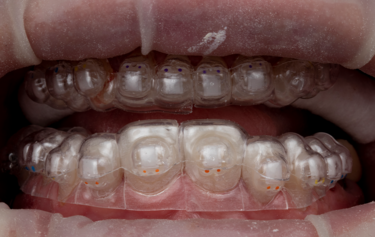

Figure 7: Indirect orthodontic bracket bond-up stents in-situ

Figure 8: Immediate result after stent-guided composite build-up and orthodontic bracket placement

The full restoration of all the patient’s upper and lower teeth was completed using this process at the same visit in only 2 hours. We were able to immediately then place upper and lower orthodontic brackets using an in-direct set-up technique through CFast orthodontics. This stent-guided application method means a much quicker and simpler fixation of the bracket to the teeth. Due to the incredible accuracy of the SmileFast stent, the composite restorations placed are a perfect replication of the digital model on which the orthodontic set-up was manufactured, therefore the stent for the orthodontics was a perfect fit, as shown in Figure 7. Within 4 hours all the patient’s teeth were fully restored and the fixed orthodontics applied and activated with 0.014 NiTi wires (Fig. 8). After 5-months the teeth were aligned into a more favourable position and the passive over-eruption of the teeth had been reversed (Fig.9). The patient was comfortable and occlusion functioning well, so it was decided to move forward with the second phase of her rehabilitation, the planning and provision of her final ceramics.